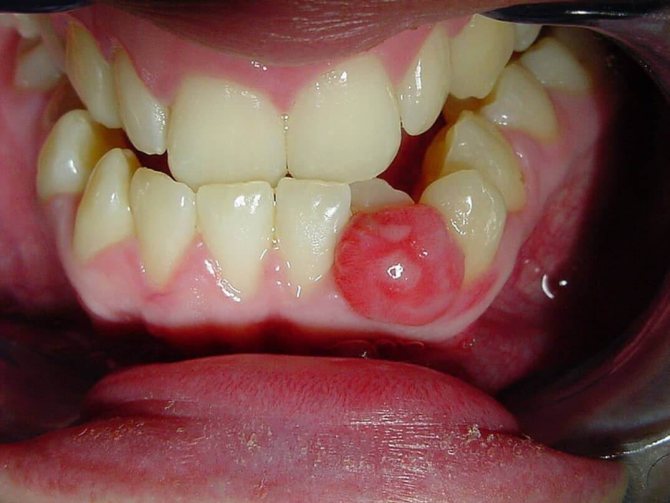

Нарост на десне.

- Цветом – зависит от разновидности нароста. Так, фиброзный идентичен по окрасу с десной, гигантоклеточная – буро-коричневая или синюшная, ангиоматозный – бывает от ярко-красного до темно-красного. Если его часто травмировать пломбой, зубами, протезными кламмерами, его поверхность сильно изъявляется и изменяет окрас.

Ангиоматозное образование

По эстетическим соображениям фото эпулиса на десне не представлены в данной статье. Давайте охарактеризуем ангиоматозную опухоль:

- Внутри образования наблюдается частая сеть мелких кровеносных сосудов.

- Чаще всего встречается у детей 5-18 лет. Группа риска — 5-10 лет.

- Локализация: шейки зубов.

- Внешне напоминает скопление маленьких бугорков. В редких случаях поверхность будет гладкой.

- Цвет опухоли неестественный: ярко-алый, синеватый.

- Основание образования будет плотным и широким.

- Консистенция опухоли твердая и плотная.

- При малейшем повреждении ангиоматозный эпулис начинает кровоточить.

- Опухоль быстро увеличивается в размерах. Кроме того, после ее удаления возможен рецидив.